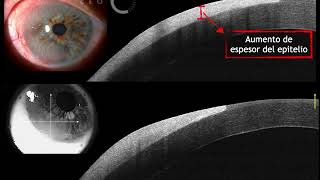

Multi CEO - Neoplasia intraepitelial corneal

Multi CEO - Neoplasia escamosa de la superficie

NEOPLASIA INTRAEPITELIAL CORNEAL (CIN) A PROPÓSITO DE UN CASO DR. FRANCISCO FERRO

Neoplasia intraepitelial corneal - Dr. Andrés Contreras